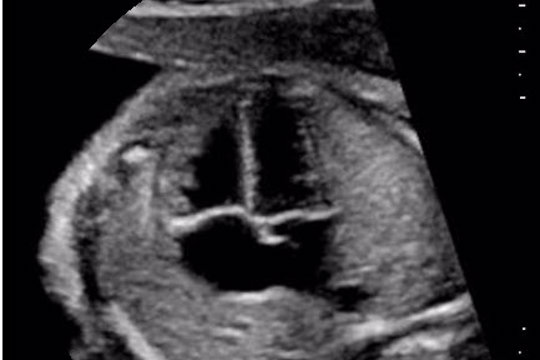

Fetaler Echo-Aufbaukurs

D1/2024 - Fetale Echokardiografie Kursreihe 2024